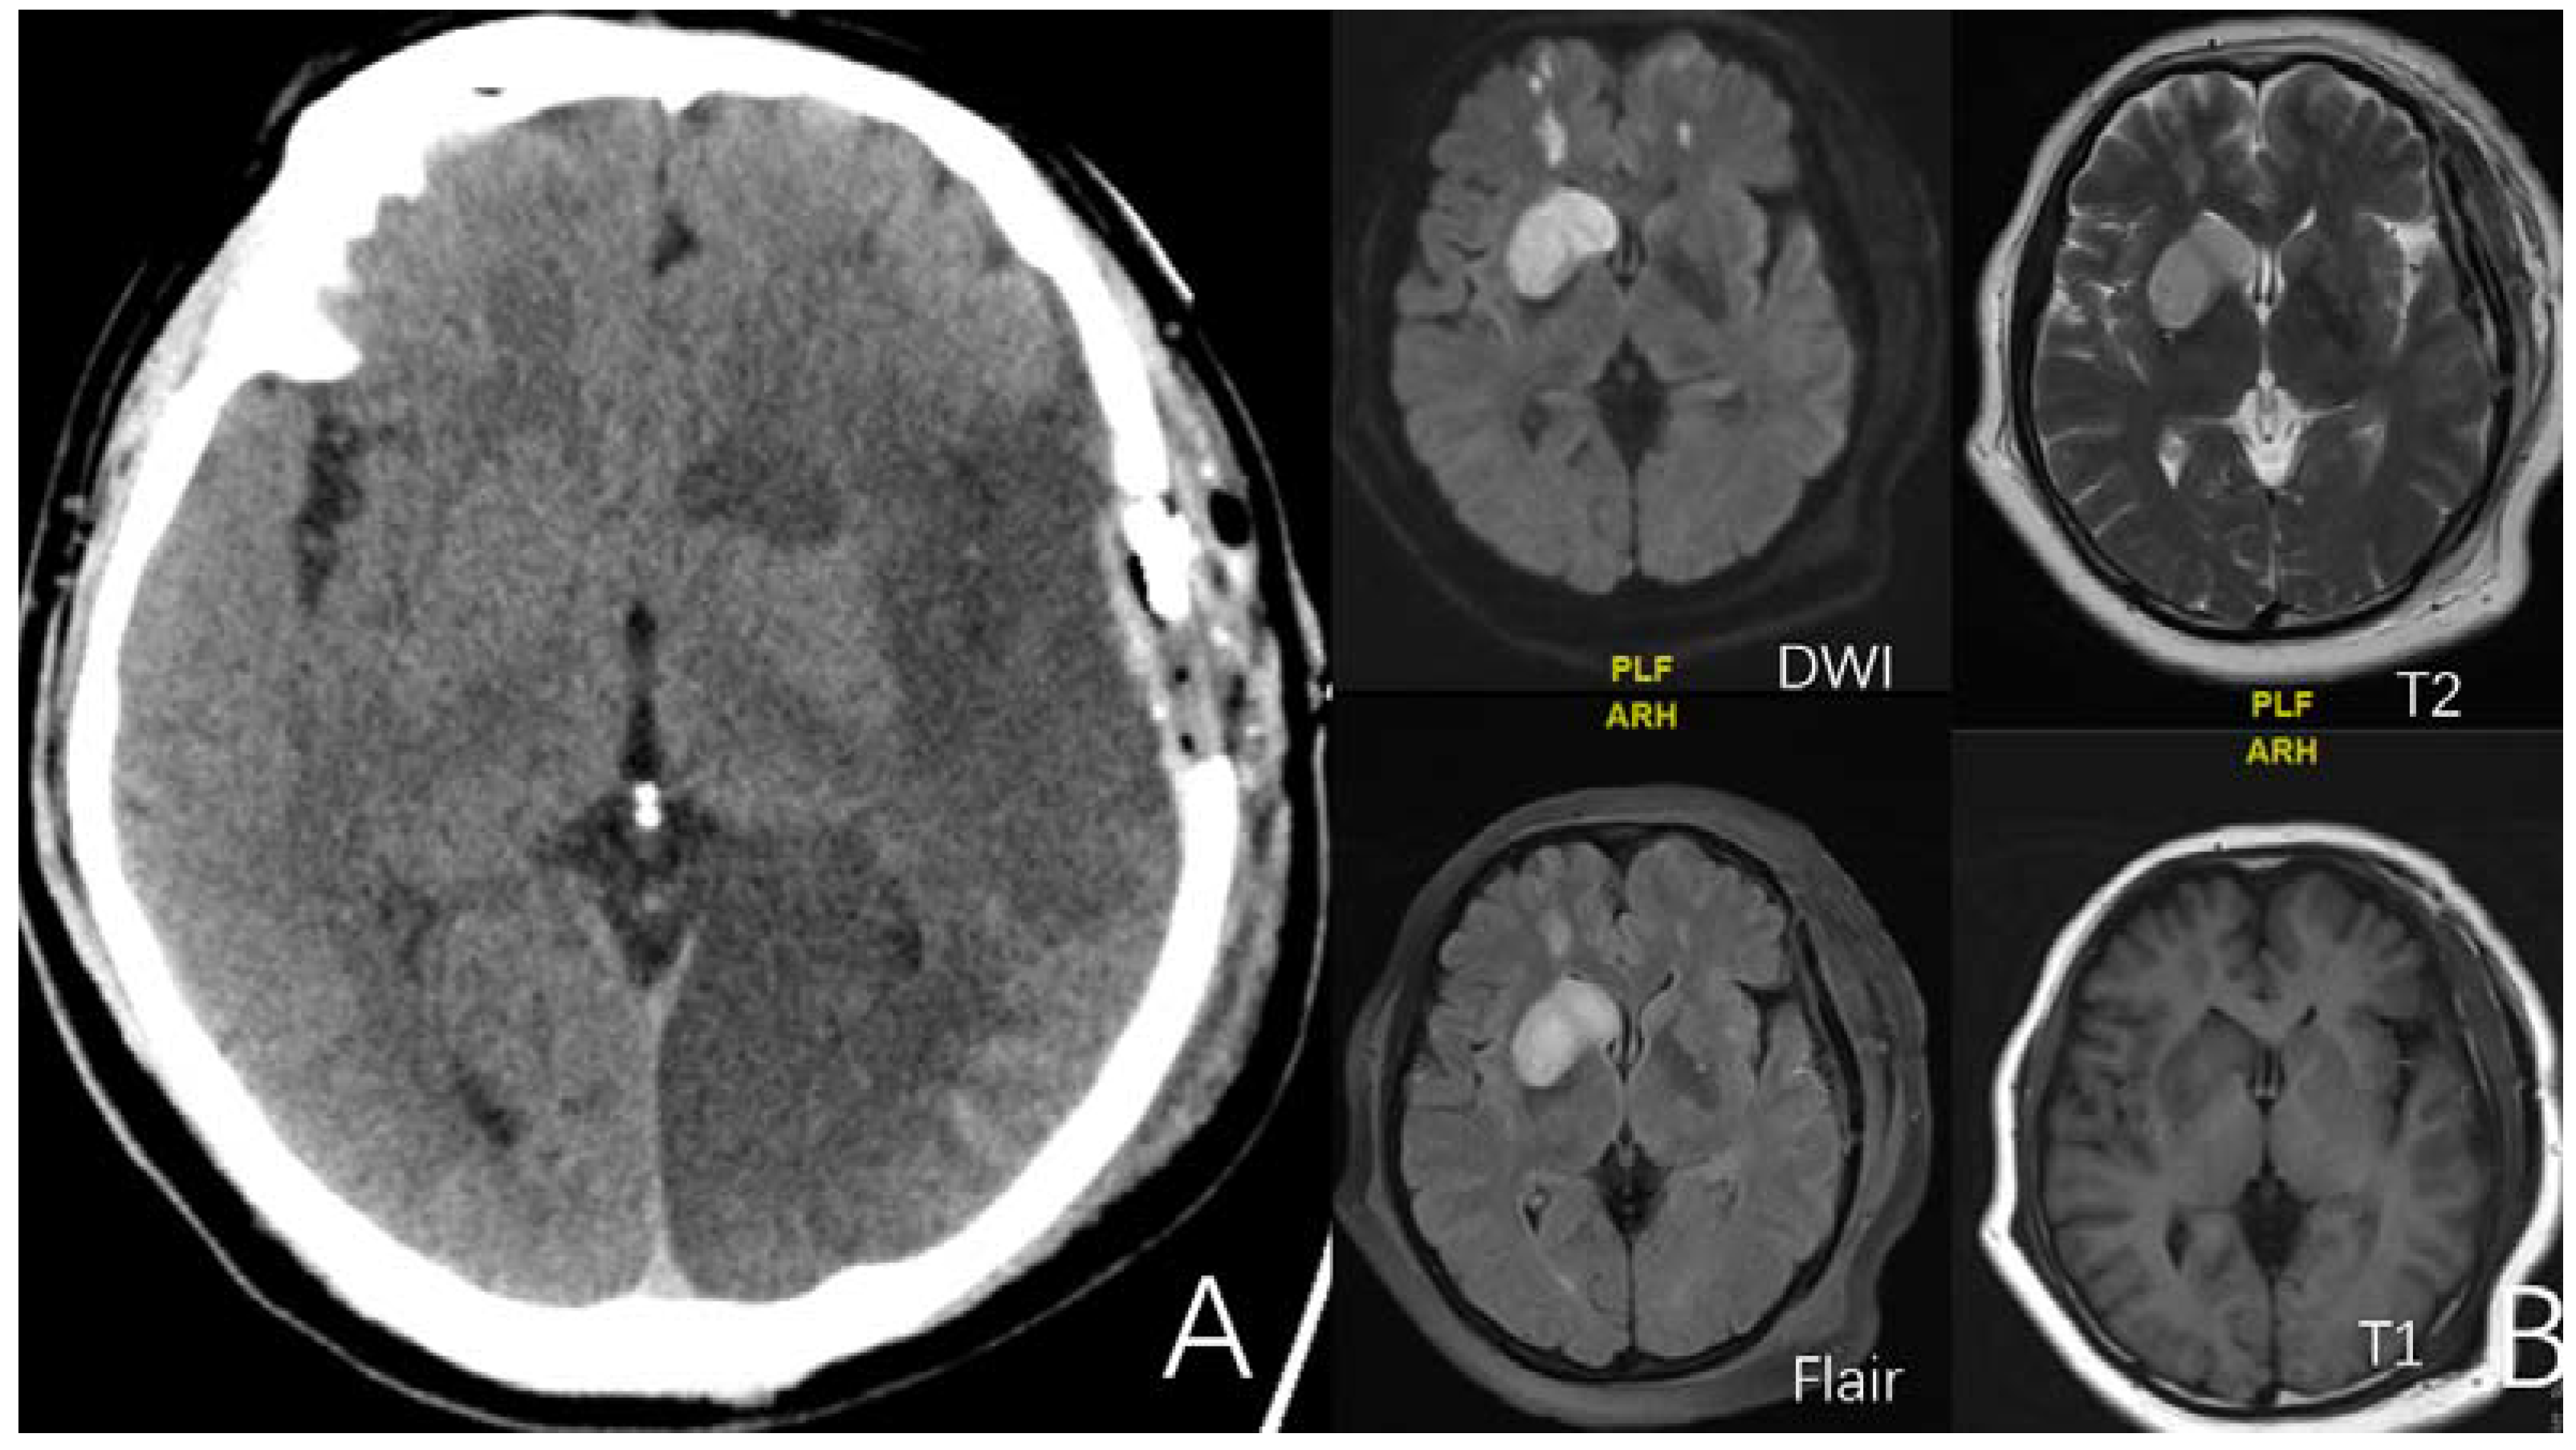

2.3.5. Old Cerebral Infarction

2.3.6. Factor 1 ICA Stenosis

2.3.7. Factor 2 A1 Stenosis

2.3.8. Factor 3 M1 Stenosis

2.3.9. Factor 4 PCA Anomaly

2.3.11. Factor 6 Unstable Compensation